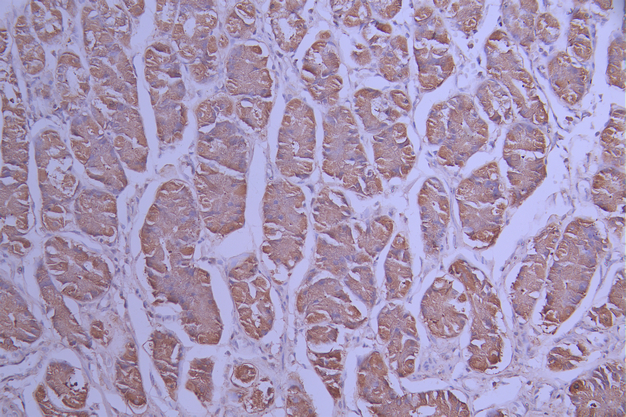

IHC image of CSB-RA907805A0HU diluted at 1:100 and staining in paraffin-embedded human stomach tissue performed on a Leica BondTM system. After dewaxing and hydration, antigen retrieval was mediated by high pressure in a citrate buffer (pH 6.0). Section was blocked with 10% normal goat serum 30min at RT. Then primary antibody (1% BSA) was incubated at 4°C overnight. The primary is detected by a Goat anti-rabbit polymer IgG labeled by HRP and visualized using 0.05% DAB.